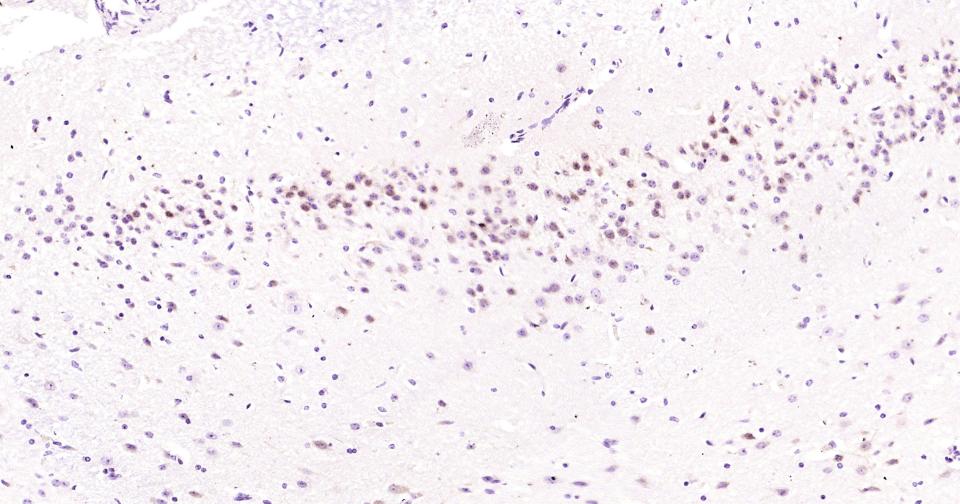

Paraformaldehyde-fixed, paraffin embedded Mouse Cerebrum; Antigen retrieval by boiling in sodium citrate buffer (pH6.0) for 15 min; Antibody incubation with JNK1 Monoclonal Antibody, Unconjugated(bsm-61084R) at 1:200 overnight at 4°C, followed by conjugation to the bs-0295G-HRP and DAB (C-0010) staining.

Paraformaldehyde-fixed, paraffin embedded Rat Cerebrum; Antigen retrieval by boiling in sodium citrate buffer (pH6.0) for 15 min; Antibody incubation with JNK1 Monoclonal Antibody, Unconjugated(bsm-61084R) at 1:200 overnight at 4°C, followed by conjugation to the bs-0295G-HRP and DAB (C-0010) staining.